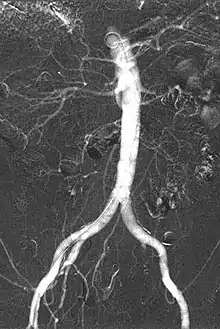

Carbon dioxide angiography is a diagnostic radiographic technique in which a carbon dioxide (CO2) based contrast medium is used - unlike traditional angiography where the contrast medium normally used is iodine based – to see and study the body vessels. Since CO2 is a non-radio-opaque contrast medium, angiographic procedures need to be performed in subtraction angiography (DSA).

Carbon dioxide is a negative contrast medium and it has a low radiopacity (while iodinated contrast media are defined as positive contrast media due to their high radiopacity). Contrast is caused by the different X-ray absorption coefficients between the tissue and the contrast agent. In the vascular imaging results produced using CO2, vessels look brighter rather than the surrounding tissues, because the contrast medium absorbs less X-ray radiations rather an iodine-based contrast medium, where the vessel are displayed in black.

The CO2 does not mix with blood. At atmospheric pressure CO2 is in gaseous form and, when it comes out from the catheter, it forms a train of bubbles which displaces blood, causing a transient ischemia, in relation to the bloodstream (systolic pressure). When added together by DSA “stacking” software,[4] the result is a composite diagnostic image of the frames.